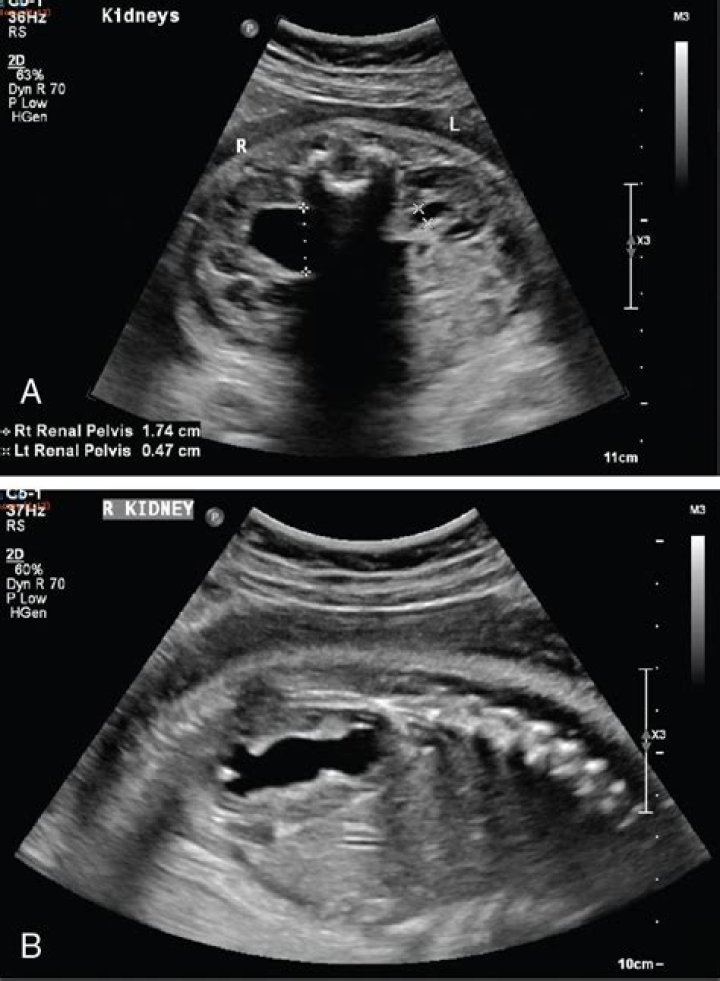

Fetal hydronephrosis is swelling of a baby’s kidney caused by a buildup of urine. This can happen while the baby is still in the mother’s uterus. Doctors often find the problem when a woman has a fetal ultrasound during pregnancy. Urine normally travels from the kidney down a narrow tube to the bladder.

Fetal hydronephrosis is one of the most common problems detected by prenatal ultrasounds. It affects approximately 1 out of every 100 newborns. Unborn babies with fetal hydronephrosis do not typically experience problems in the womb. In half of all cases, the condition resolves on its own by the third trimester.